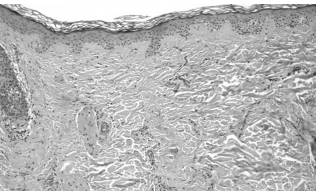

Рис. 1. Очаги красного плоского лишая

Рис. 2. Очаги красного плоского лишая

Рис. 3. Очаги красного плоского лишая

Рис. 4. Очаги красного плоского лишая

Пациент А., 43 года, обратился с жалобами на высыпания на коже волосистой части головы, лица, выпадение и отсутствие роста волос на коже волосистой части головы, подмышечных впадин и лобка, сопровождающиеся периодическим зудом (рис. 1–4).

Из анамнеза заболевания: высыпания впервые появились более пяти лет назад на коже волосистой части головы, в связи с чем дерматолог по месту жительства выставил диагноз «красный плоский лишай». Пациент использовал глюкокортикоиды для наружного применения без видимого эффекта. Впоследствии высыпания распространились на кожу лица, подмышечные впадины и пах. Последние два года пациент стал отмечать выпадение волос на коже головы, подмышечных впадин и лобка. Со стороны внутренних органов патологических изменений не выявлено. Клинические и биохимические анализы без особенностей.

При осмотре: на коже волосистой части головы, лица, подмышечных впадин и паховой области множество мелких фолликулярных, остроконечных узелков телесного цвета с небольшими роговыми шипиками на верхушке без признаков воспаления. При поглаживании кожа представляется сухой, жесткой, шероховатой и создает впечатление терки. На волосистой части головы, в области темени, затылка и висков, имеются небольшой величины очаги выпадения волос круглой или овальной формы. Местами очаги алопеции сливаются и образуют участки значительной величины (3×4–5×7 см) с фестончатыми очертаниями. Кожа в пределах очагов облысения натянута, блестит, атрофична и как бы вдавлена, окраска нормальная. По периферии очагов алопеции располагаются фолликулярные конусовидные узелки. Волосы в подмышечных ямках и на лобке разрежены, часть их обломана и истончена (нерубцовые участки облысения) (рис. 5).